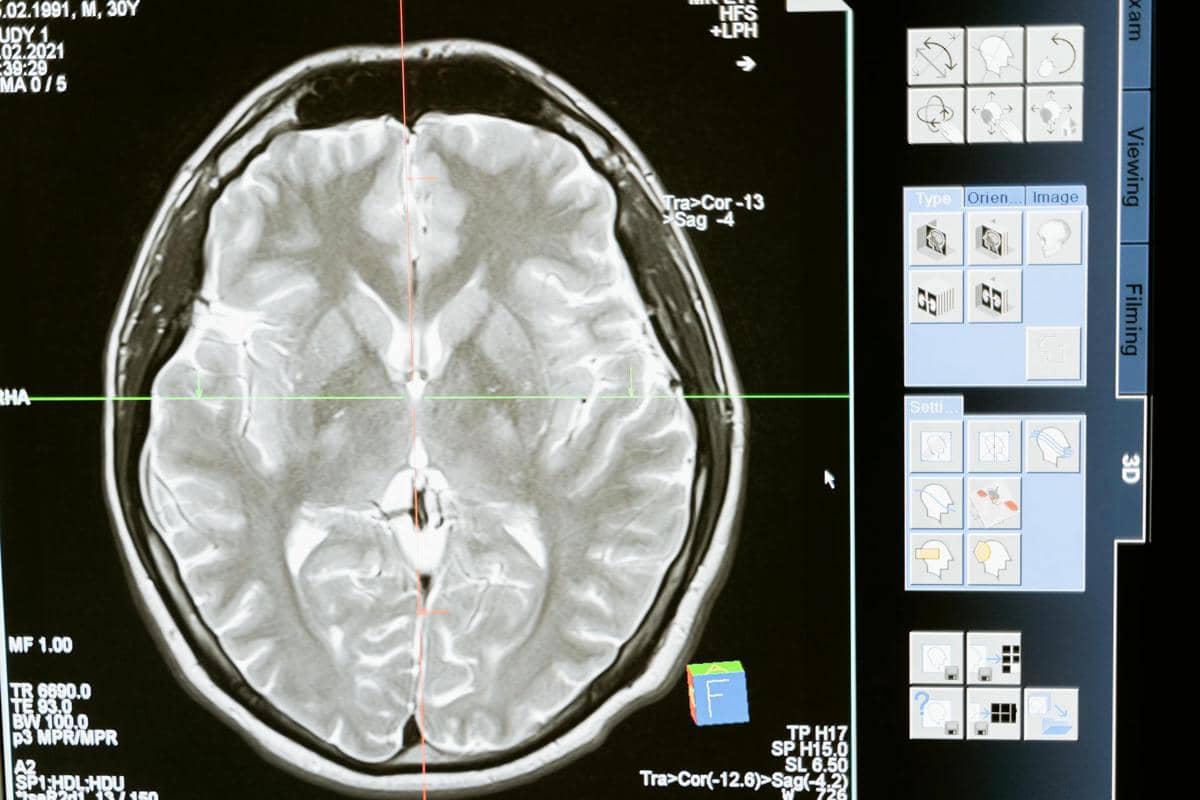

Glioma adalah jenis tumor otak yang berasal dari sel glial, yaitu sel-sel yang berfungsi mendukung dan melindungi neuron di sistem saraf pusat. Tumor ini dapat tumbuh di otak maupun sumsum tulang belakang dan sifatnya bisa jinak maupun ganas.

Penyakit yang menyerang pusat kendali tubuh ini dapat memengaruhi berbagai fungsi tubuh tergantung pada lokasi dan ukuran tumornya. Kondisi ini termasuk dalam kategori penyakit serius karena dapat berkembang dengan cepat dan menimbulkan tekanan pada jaringan otak yang sehat.